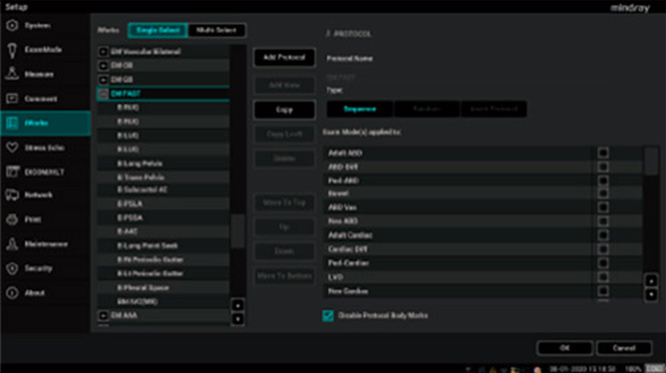

Ons doel is de druk op het personeel van de spoedeisende hulp te verlichten, de snelheid en nauwkeurigheid van de klinische besluitvorming te verbeteren en het leven van pati?nten verder veilig te stellen. Daarom hebben we de ME Series POC Ultrasound ontworpen gericht op een workflow voor noodgevallen. Er zijn door de gebruiker gedefinieerde instellingen om prioriteit te geven aan de meest gebruikte sondes en scanworkflows, zodat met ├®├®n klik kan worden omgeschakeld. Ook zijn er diverse snelle echografieprotocollen voor aan het bed ingebouwd, zoals FAST en EFATE, zodat artsen in geval van nood snel en adequaat de status van de pati?nt kunnen beoordelen.

Protocollen voor spoedonderzoeken in de POC Ultrasound van Mindray.

Ons doel is de druk op het personeel van de spoedeisende hulp te verlichten, de snelheid en nauwkeurigheid van de klinische besluitvorming te verbeteren en het leven van pati?nten verder veilig te stellen. Daarom hebben we de ME Series POC Ultrasound ontworpen gericht op een workflow voor noodgevallen. Er zijn door de gebruiker gedefinieerde instellingen om prioriteit te geven aan de meest gebruikte sondes en scanworkflows, zodat met ├®├®n klik kan worden omgeschakeld. Ook zijn er diverse snelle echografieprotocollen voor aan het bed ingebouwd, zoals FAST en EFATE, zodat artsen in geval van nood snel en adequaat de status van de pati?nt kunnen beoordelen.

Protocollen voor spoedonderzoeken in de POC Ultrasound van Mindray.